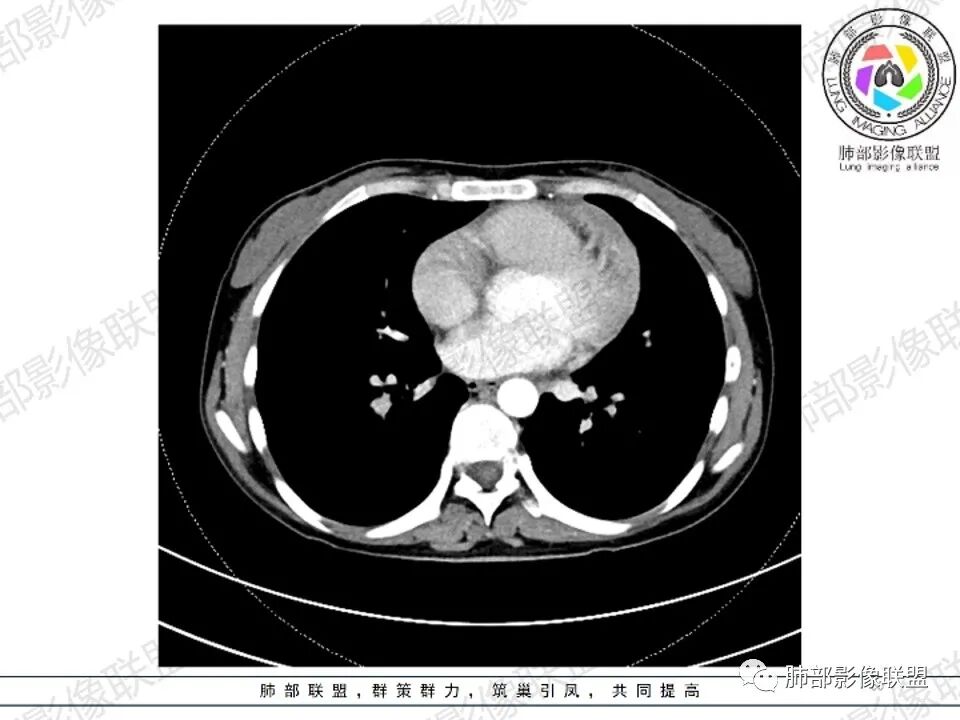

2.影像显示前纵隔不规则块状影,依势贴附心脏大血管旁,密度不均,边界不甚清楚,有结节融合感。

3.病灶轻度不均匀强化,可见血管穿行,散在液性低密度区。

双肺门未见肿大淋巴结。

4.双侧腋窝区见增大淋巴结,边界清楚。

1.年轻女性,前纵隔不规则块状影,密度不均,边界不甚清楚,有结节融合感,轻度不均匀强化,可见血管穿行,最常见最符合的无疑是淋巴瘤!